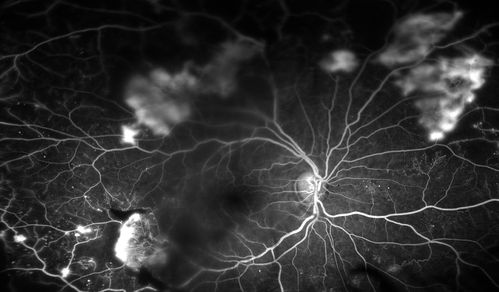

Fluorescence Angiography of BDR

Patient is here for eval on diabetic retinopathy. FA photos show significant diabetic retinopathy with hemorrhage inferior temporal to the optic nerve.

Mayo Clinic Jacksonville, Florida

OPTOS 200TX